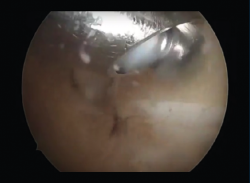

Figura 4. Observación de la cola del astrágalo por artroscopia posterior de tobillo.

En caso de que el tratamiento conservador fracase, se puede proceder a una artroscopia posterior de tobillo (Figura 3), que consistirá en la exéresis de fragmentos óseos (Figura 4), la regularización de la anatomía redundante, la limpieza del FLH, la liberación del retináculo flexor o el inicio del túnel, u otro gesto dirigido a la etiopatogenia del dolor(6).

La etiología de la lesión había sido atraumática en 8 casos y hubo una fractura como causa inicial en 1 caso (Figura 5). En una media de 128 minutos de intervención, hubo 6 exéresis de os trigonum (Figura 6), 2 exéresis de Stieda y 5 sinovectomías del tendón FLH como procedimientos principales (Figura 7). En 3 casos se completó la técnica quirúrgica con artroscopia del compartimento anterior y en 1 caso se añadió una artrodesis subastragalina (Figura 8). La artrodesis fue planteada debido a una artrosis subastragalina ya presente en los estudios previos a la intervención, en una paciente con patología reumática de base (sinovitis villonodular).